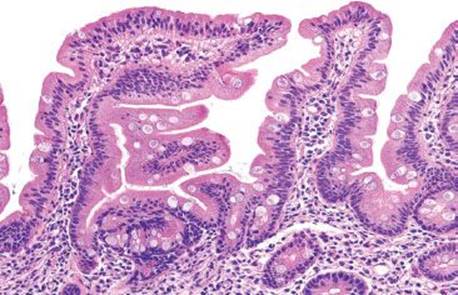

Figure 2.120 Lymphocytic gastritis pattern. This pattern of injury characteristically includes a mononuclear infiltrate in the lamina propria, but it differs from other types of chronic gastritis by the presence of increased intraepithelial lymphocytes (IELs), defined as >25 IELs per 100 epithelial cells.

Lymphocytic gastritis differs from chronic gastritis by the presence of increased intraepithelial lymphocytes (IELs), defined as more than 25 intraepithelial lymphocytes per 100 epithelial cells (Figs. 2.120–2.126).38,91–97 The term “lymphocytic gastritis” was originally used to describe the histologic counterpart to “varioliform” gastritis (i.e., thickened rugal folds and erosions), but subsequent studies have shown this association in only 3.9% to 30% of cases. More commonly, the endoscopic image shows erythema but up to 50% of patients have a normal endoscopic appearance. Although the etiology of the inflammation remains unknown in up to 20% of cases, common associations include infection (e.g., Helicobacter, HIV), celiac disease and other immune-mediated disorders (common variable immunodeficiency, Crohn disease, lymphocytic enterocolitis), medications, and neoplasia (Figs. 2.127–2.142).98 As a result, recognition of the lymphocytic gastritis pattern can serve as an important red flag to the underlying diagnosis and, consequently, lead to effective therapy with resolution of symptoms. The changes affect the entire stomach, but intraepithelial lymphocytes are most evident in the oxyntic mucosa, and are more prominent in the superficial epithelium than the glands. Most cases show expansion of the lamina propria with a mixed lymphoplasmacytic inflammatory infiltrate, in addition to the intraepithelial lymphocytosis (Fig. 2.121). Regenerative and hyperplastic changes in the surface epithelium may be present, analogous to the surface changes seen with intraepithelial lymphocytosis of the small and large bowel. Immunolabeling identifies these as CD3+ T cells, with about 80% showing a cytotoxic/suppressor CD8+ phenotype. Most patients respond to treatment of their associated condition, when a known etiology is present (i.e., successful eradication of Helicobacter usually leads to reduced symptoms and decreased inflammation in biopsies, and adherence to a gluten-free diet typically results in clinical and histologic improvement in patients with celiac disease). Others advocate empiric Helicobacter eradiation, even in Helicobacter-negative patients. In general, immunosuppressive medications are reserved for those who fail gluten withdrawal and whose intraepithelial lymphocytosis involves the stomach, small, and large bowel. Untreated lymphocytic gastritis may persist for years, although spontaneous remission has been reported.

Figure 2.121 Lymphocytic gastritis pattern. The changes of lymphocytic gastritis are often prominent enough that they can be identified at scanning magnification, obviating the need for intraepithelial lymphocyte counts. The IELs usually affect the entire stomach but are more evident in the oxyntic mucosa and are more prominent in the superficial epithelium as compared to the deeper glands. Note the diffuse mixed inflammatory infiltrate in the lamina propria.